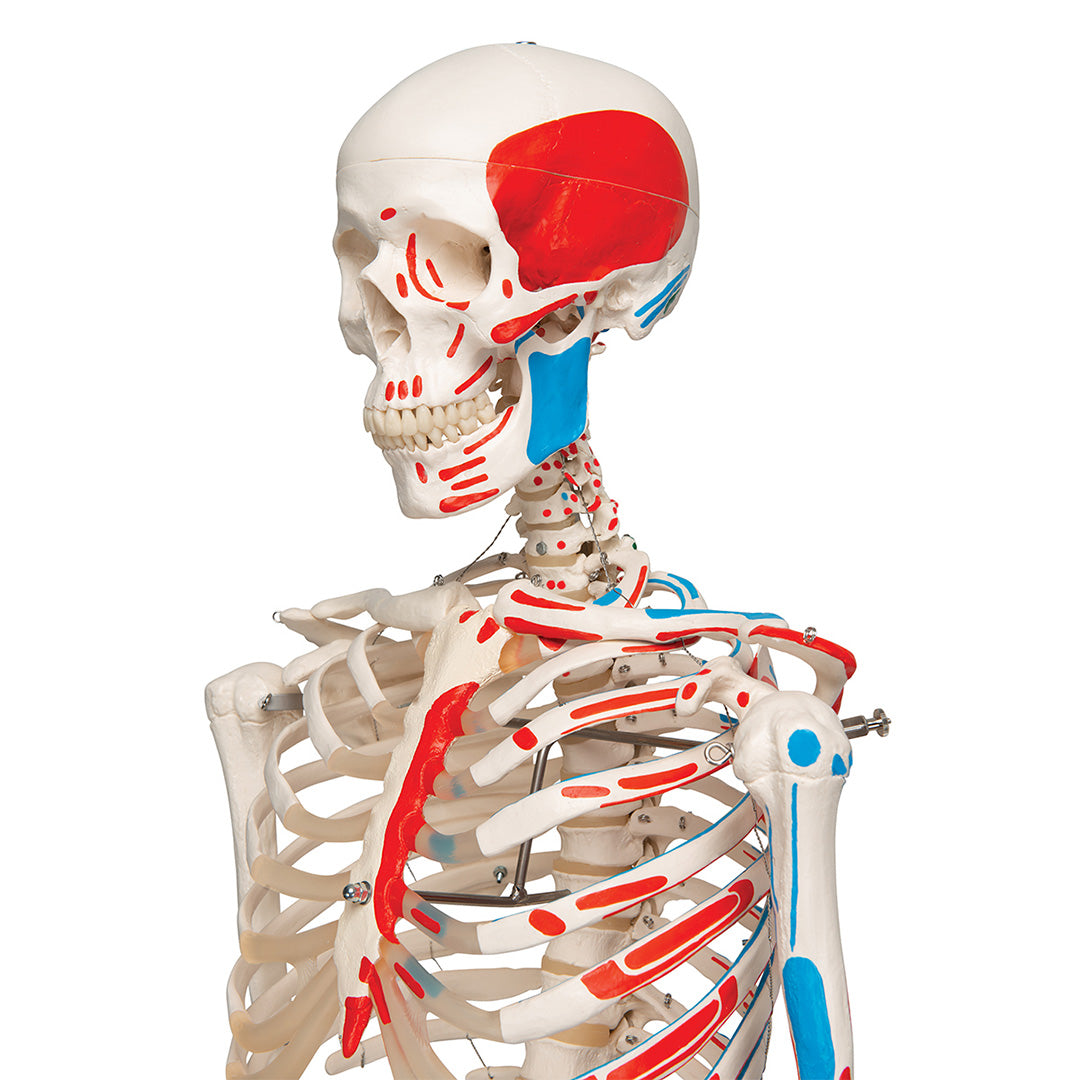

Esqueleto Max A11 Con músculos y sobre pie metálico con 5 ruedas

Esqueleto Max A11 Con músculos y sobre pie metálico con 5 ruedas

Max, posee todas las ventajas de un esqueleto de ofreciéndonos además la interacción entre los músculos y el esqueleto.

En su lado izquierdo se designan hasta 600 estructura anatómicas médicamente relevantes, como los nacimientos de los músculos (rojo), las inserciones musculares (azul), así cómo los huesos numerados a mano, cisuras y forámenes sobre la mitad derecha.

Características

• Fabricado con material plástico irrompible

• Sobre pie metálico con 5 ruedas (lacado en blanco)

• Peso similar al natural de los aproximadamente 200 huesos

• Esqueleto de tamaño natural

• Anatómicamente correcto

• Cráneo de tres piezas

• Dientes montados cada uno por separado

• Los diferentes miembros pueden desmontarse de manera fácil y rápida

Se entrega con el pie incluido y una funda guardapolvo transparente.

Peso 9.895 kg

Dimension 176.5 cm